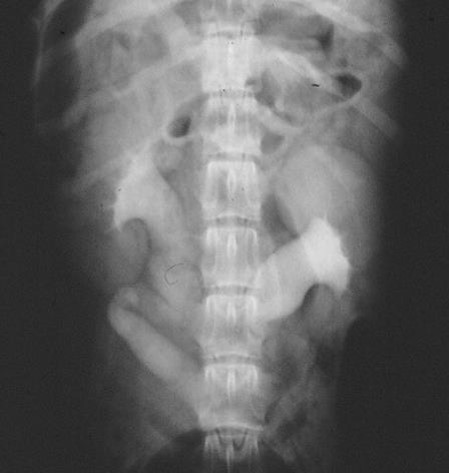

what is this?

Dilation of renal pelvis

Chunky ureters

What is going on?

Hydronephrosis/ dilated ureters